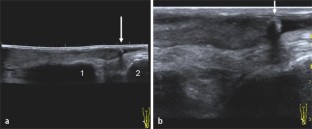

Abb. 1